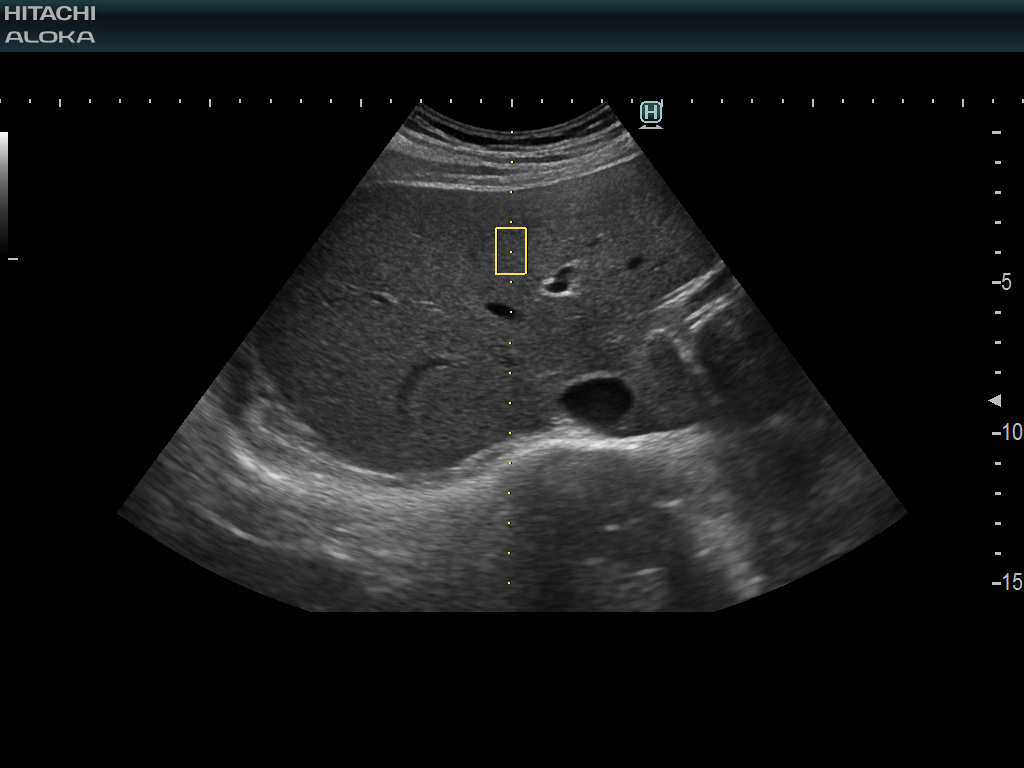

193/5000 RTE는 실시간으로 조직 변형을 평가하고 조직 강성의 측정 된 차이를 컬러 맵으로 표시하여 예를 들어 C 형 간염 환자의 섬유증 병기 결정을 추정합니다.

145/5000 조직의 평가를 허용하고 전단파 속도 측정의 객관적인 평가를위한 추가 신뢰성 지표를 제공합니다.